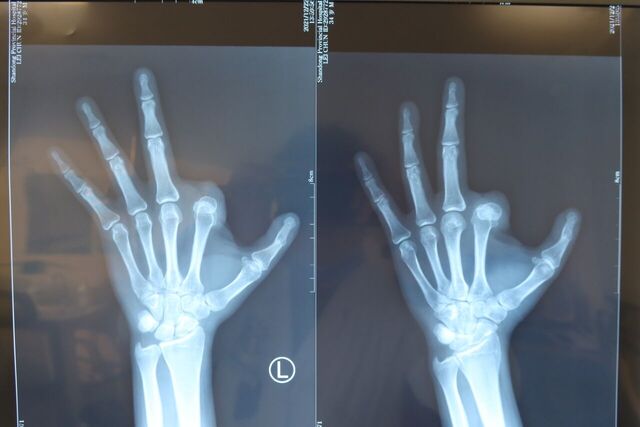

示指再造 1.5月随访